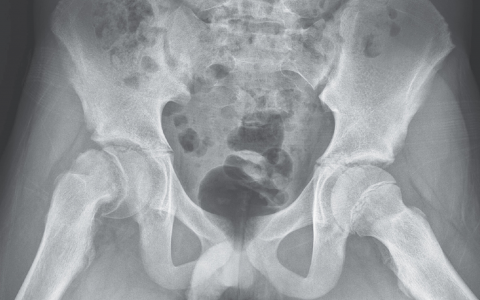

An 80-year-old man is brought to the emergency department by his daughter after suffering a seizure. For months he has taken exceptionally short steps, unable to raise his legs. He is incontinent of urine and does not “know when to go.” His recent memory is also impaired, and he denies having fallen despite evidence to the contrary. There is no history of stroke or intracranial mass lesions. On neurologic examination cranial nerves are intact, muscle strength is normal, and sensorium is normal. The patient sways during Romberg’s test with eyes open or closed. A CT scan of the head is shown in the image. Cerebrospinal fluid pressure is normal. What is the most likely etiology of the dilated ventricles?

该患者有正常压力脑积水(NPH),这是一种以脑室慢性扩张为特征的老年人疾病。NPH患者通常表现为以下临床三联征:尿失禁、步态困难和智力下降(记住:“湿、摇晃和古怪”)。虽然确切的机制尚不清楚,但NPH被认为是一种交通性脑积水,其中脑脊液(CSF)重吸收在蛛网膜绒毛受损。